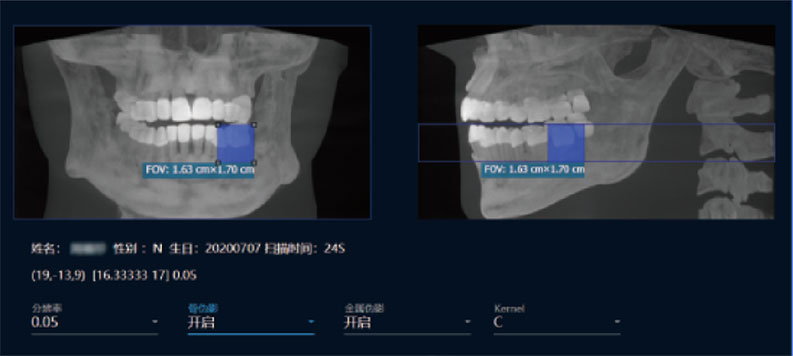

支持局部超清三维显示

局部超清显示、 移动视野摄片

真人正侧位投影,实现CT成像区域无极可调

可根据临床需求任意调整成像区域大小实现局部超清三维显示

可根据临床需求任意调整成像区域大小实现局部超清三维显示

临床样片